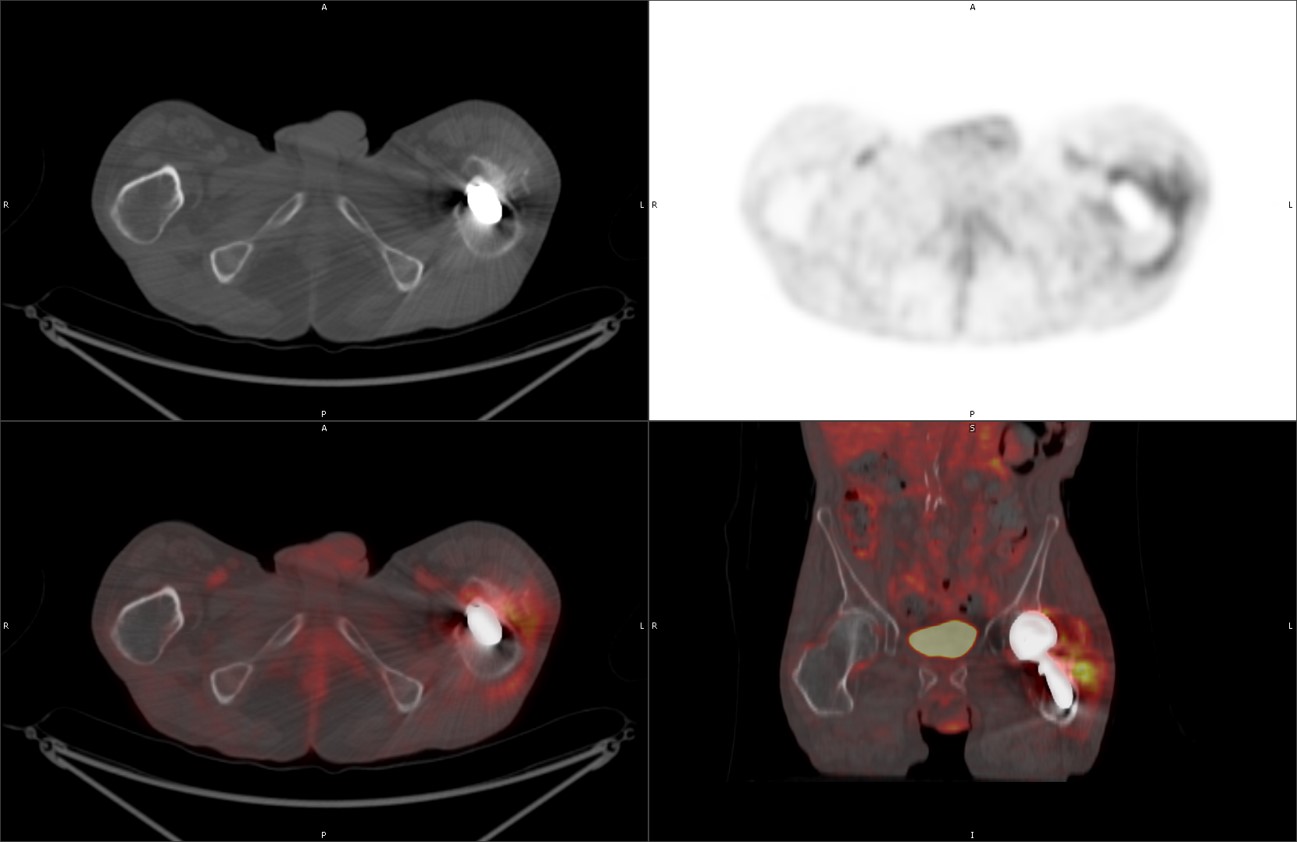

60 year-old man with history of lung cancer and left hip arthroplasty suffered from stiffness in the left hip region. Axial CT, FDG PET, fused axial, and coronal PET-CT demonstrates increased uptake of FDG in heterotopic ossification in the musculature of the left thigh. |